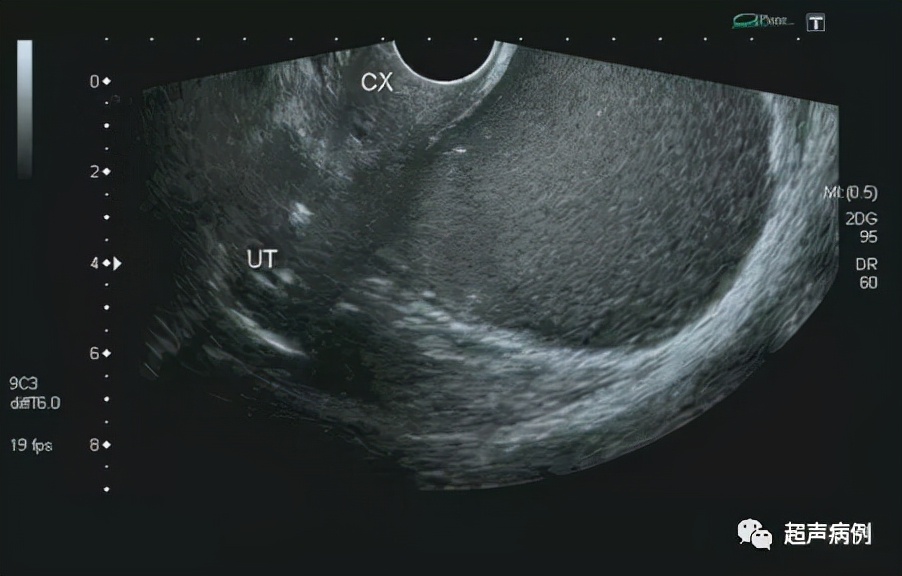

超声检查:

前位子宫,形态、大小正常

在子宫后方盆腔内查见一约10.4x9.7x7.3cm无回声区

形态规则,边界清楚,内透声差,呈毛玻璃样改变

内可见强回声分隔

CDFI:该无回声区内部及周边未见明显血流信号。

双侧卵巢显示不清。